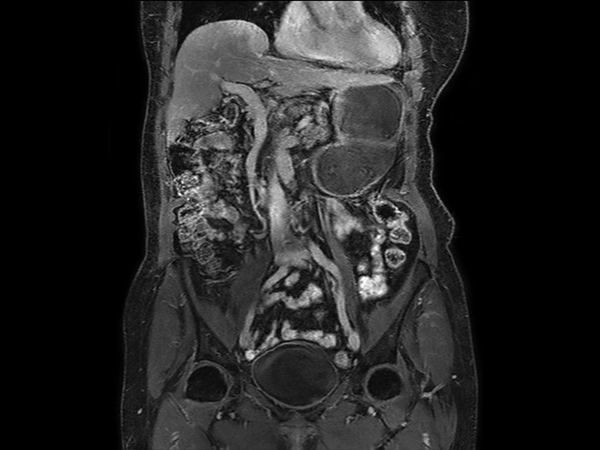

Coronal T2w TSE dS SENSE = 5, FOV 480 mm